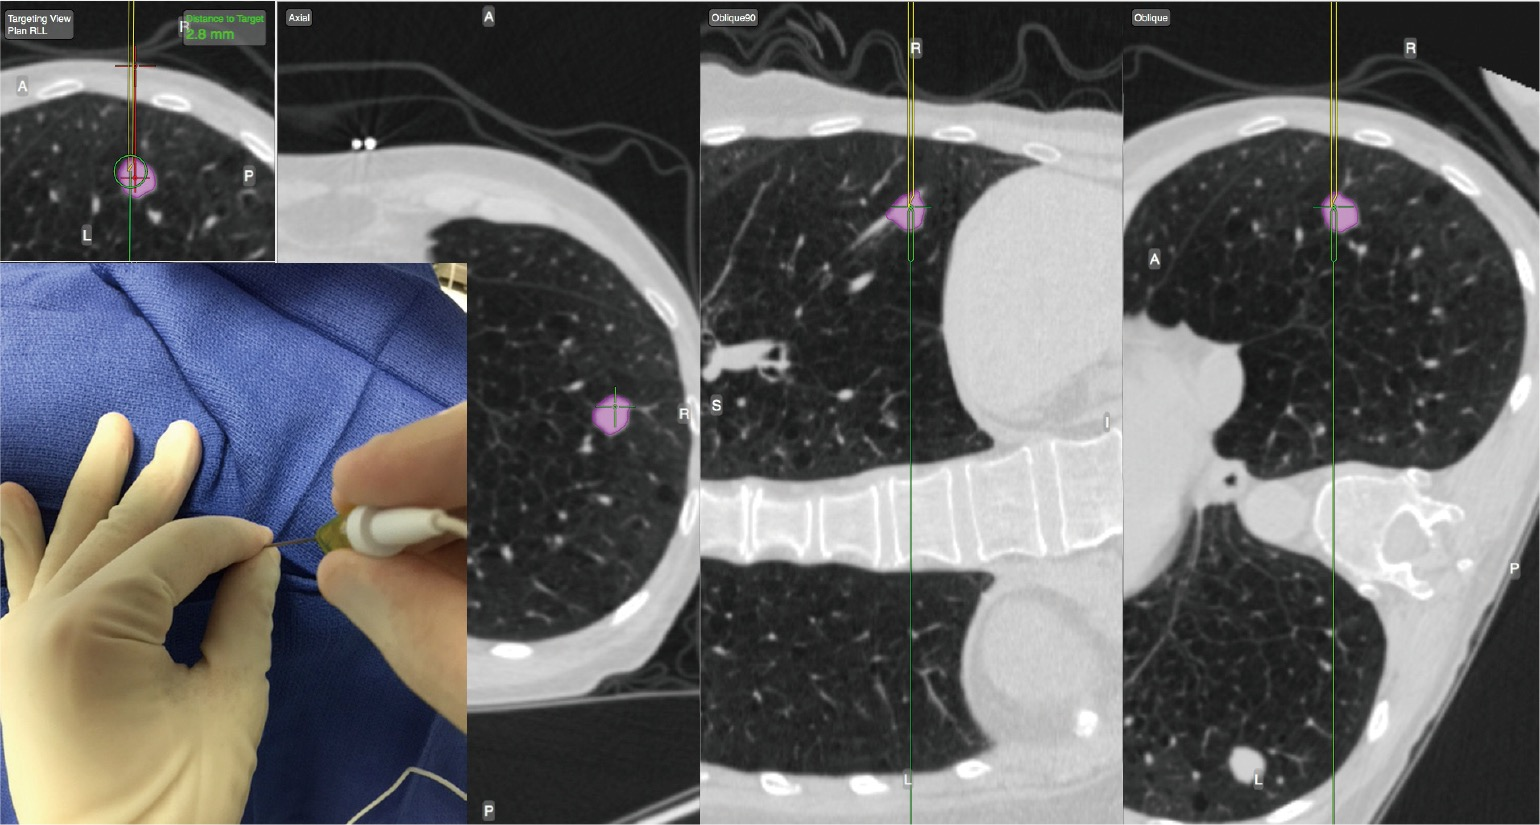

Tomography Free FullText Accuracy of CTGuided CoreNeedle Biopsy Transthoracic Needle Aspiration Definition Transthoracic needle aspiration biopsy (tnab) is a useful diagnostic technique in the evaluation of thoracic disease. Percutaneous transthoracic needle biopsy (ptnb) is one of the essential diagnostic procedures for pulmonary lesions. Transthoracic aspiration refers to a medical procedure involving needle aspiration of a suspected pneumonia area to obtain a clinical. Percutaneous lung lesion biopsy (pllb) is a procedure that involves. Transthoracic Needle Aspiration Definition.

CT guided transthoracic needle biopsy from a lesion in left lungs upper Transthoracic Needle Aspiration Definition Transthoracic needle aspiration (ttna) has been used to diagnose disease in the lung for many decades. Transthoracic needle aspiration refers to percutaneous biopsy performed with a help of imaging guidance, usually ct. Transthoracic needle aspiration biopsy (tnab) is a useful diagnostic technique in the evaluation of thoracic disease. Percutaneous lung lesion biopsy (pllb) is a procedure that involves passing a. Transthoracic Needle Aspiration Definition.

CTGuided Transthoracic Needle Aspiration Biopsy of Subsolid Lung Transthoracic Needle Aspiration Definition Transthoracic aspiration refers to a medical procedure involving needle aspiration of a suspected pneumonia area to obtain a clinical. Percutaneous lung lesion biopsy (pllb) is a procedure that involves passing a needle percutaneously under image guidance. Transthoracic needle aspiration refers to percutaneous biopsy performed with a help of imaging guidance, usually ct. Transthoracic needle aspiration biopsy (tnab) is a useful. Transthoracic Needle Aspiration Definition.